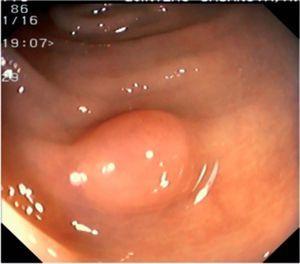

Fig. 4. Examples of protruding lesions with conventional examination and after the application of indigo carmine 0.2-0.5%. a, b) Sessile polyp. c, d) Subpedunculated polyp. e, f) Pedunculated polyp. g, h) Submucosal lesion (indigo carmine shows distinct innominate grooves, ruling out an epithelial lesion). i) Subpedunculated polyp. j) After indigo carmine application, a flat elevated lesion similar in size to the protruding segment is clarified.